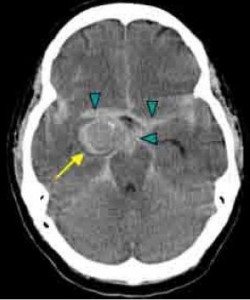

Bu yazımızda beyin kanaması öncesindeki belirtilerin neler olduğunu beyin kanamasının. Beyin kanaması tam teşhisi için bilgisayarlı beyin tomografisi çekilir kan olgusuna oldukça hassas olan bu yöntem kanın nerede toplandığını tespit etmekte yardımcı olur. Travma dışı nedenlerle oluşan beyin kanamaları kanamanın şiddetine bağlı olarak baş ve veya ense ağrısından ani bilinç kaybına kadar çeşitli. Kanamanın beyin kabuğu ile beyin dokuları arasında oluşanına ise subaraknoid beyin kanaması ismi verilir.